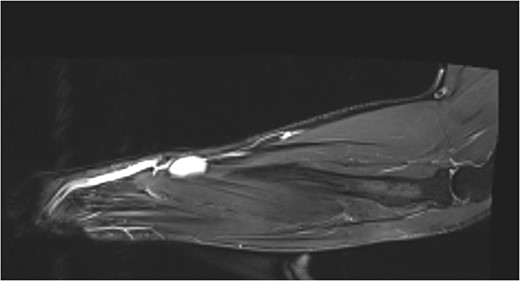

A subsequent MRI, showed a hyper intense 23 × 5 × 15 mm subcutaneous mass, with prominent adjacent feeding vessels, overlying the muscle bellies of abductor pollicis longus and extensor pollicis brevis (Fig. 3). Radiologically, it was thought to mimic the previous ultrasound and a differential of a vascular malformation/haemangioma was favoured.

MR T1 coronal view of the left forearm showing concerning lump.